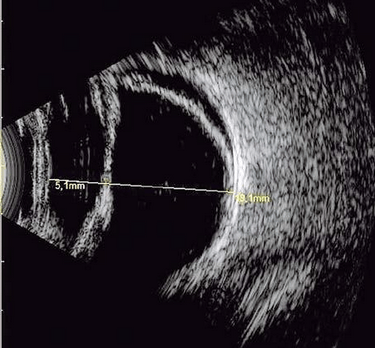

Ultrassonografia Ocular

Exame de imagem que avalia estruturas internas do olho. É Indicado quando a visualização direta é dificultada por catarata avançada, hemorragia vítrea ou opacidades. Para o diagnóstico de possíveis descolamentos de retina, patologias vitreas e tumores intraoculares